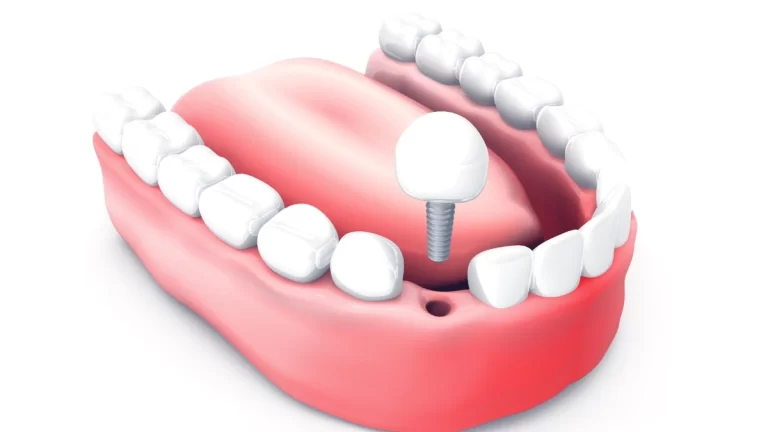

Protocolo de implantes inferior: Inovação em próteses dentárias

Descubra o que é protocolo de implantes inferior e como ele pode melhorar sua qualidade de...

Descubra o que é protocolo de implantes inferior e como ele pode melhorar sua qualidade de...

Restaure seu sorriso com segurança e conforto! Descubra o poder da protese fixa sobre implantes e...

Na minha prática profissional, gosto de me manter sempre atualizado e compartilhar com os meus pacientes...

Ao longo da minha trajetória profissional, muitos dos meus pacientes ainda se assustam ao ouvir falar...